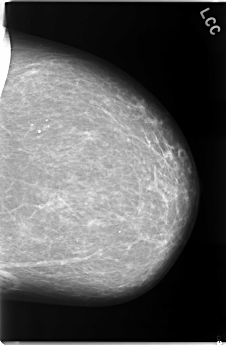

C_0083_1.LEFT_CC

LEFT_CC LINES 5864 PIXELS_PER_LINE 3840 BITS_PER_PIXEL 12 RESOLUTION 50 NON_OVERLAY